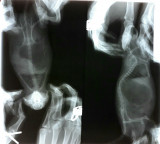

Здравствуйте! Умирает моя крыса. Но я все равно на что-то надеюсь, хотя надежды тают... Крыса Роза, примерно 2 года возраст (точно не знаю, тк у меня живет только 1 год - забрала из зоомагазина с последним крысенком после того, как ее начали активно предлагать, если я хочу самочку на развод, у них она рожала непрерывно). Возраст был заявлен 8 месяцев, но даже с учетом непрерывных родов, крысь выглядела явно старше. Очень активная, мудрая. Осенью поправилась и обросла шикарной шубой. Где-то в середине января я заметила, что она как-то похудела, но в остальном был порядок, поэтому я не беспокоилась. 14 февраля я нашла ее в клетке под поилкой сидящей на попе и смотрящей вникуда с раздутыми боками. Отсаживаем в отдельную клетку понаблюдать - крысь пьет много, правктически не ест, писяет, но за сутки не покакала. 15 февраля едем к ветеринару. В моем городе везде из рекомендованных только клиника Колибри, в которой принимает не рекомендованный врач, обращались с другой крысой, еле откачали после назначения. Поэтому едем к молодому, не рекомендованному, но он нам уже пару раз помог, там нет ни рентгена, ни узи, анализы, нам по крайней мере, никогда там не делали. Врач подозревает что-то пищевое. Но нового я ничего крысам не давала, из запрещенных вкусняшек был проверенный йогурт. Вес крысы 300г. Назначение: рингер п/к, морфлоксин в/м 0,04 1р/д, мелоксивет 0,04 в рот 1р/д, подавать энтеросгель. После мелоксивета крысе легче, но все равно я вижу, что не лучше. В правом боку нащупываем странное уплотнение примерно округлое, наощупь где-то в 1,5 см. Поэтому 19 февраля едем в клинику Панда (очень далеко, в разы дороже, но там есть все необходимое оборудование). Крысе сделали рентген (он у меня есть), узи (я присутствовала, все видела на моониторе, но, как ни странно, на руки мне ничего не дали) и несколько анализов. В крови нашли превышение мочевины - 8,1 при норме 2,4-3,4, чуть выше нормы глюкоза 7,7, гемаглобин низкий - 125, другие отклонения от нормы: С%63 (норма10-50), П% 2 (а не 0-1), ЛФ% 28 (норма 50-93), ретикулоциты++. На узи  увидели уплотнение в боку - "переродившийся" отдел печени, который пережимает большой кровеносный сосуд, в брюшине много жидкости и газов. Сердце и легкие в норме. Врач сказал, что излечение и операция в нашем случае невозможны и предложил поддерживающую терапию. Укололи метоклопрамид 0,03 в клинике и мы сами дома вечером. А дальше нам назначили гепатовет 0,1мл 2р/д поить, рингера, фуросемид на три дня 0,04 в/м 2 р/д, байтрил 5% 0,06мл в/м 2 р/д и витамин В12. На этом курсе мы увидели улучшение - крыса начала больше интересоваться едой, но продолжала много пить, по-немногу, но начала какать. Очень тосковала по своим подругам - 2 "тетки" слегка моложе ее в большой клетеке, поэтому я посадила ее к ним в большую клетку. Но вчера ей стало снова плохо, с носа прет порфирин, уже вся морда в нем, крыса вся опухла, вялая, не ест, только пьет, начала вся как будто застывать. Я дала ей мелоксивет, что дальше делать не знаю. Просто ждать когда она умрет? Возможно есть еще какой-то шанс ей помочь? Если нет, то как облегчить ее страдания?

выложите рентген здесь.

Не могу понять КАК сделать нормальное фото рентген снимка. Понимание того, что наш рентген намного хуже качеством снимков, выложенных на форуме в разделе "Архив рентгеновских снимков" пришло, но я постараюсь сделать фото как можно лучше и обязательно выложу в ближайшее время то, что имею.

на крайняк - пленку прикладываете к стеклу и фотаете на фоне горящей лампочки.. или на фоне солнечного неба